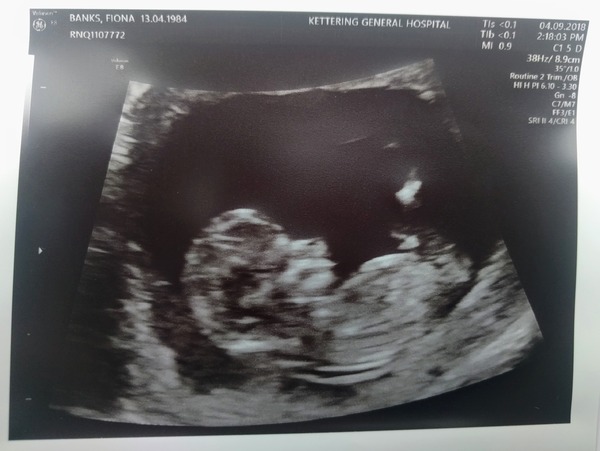

Had my booking in and scan this afternoon. Midwife struggled to measure crown to rump as baby was curled up in a ball πŸ˜‚ So cute though. Tiny heart beating so fast. She probbed about and eventually measured. EDD put back a week 😭 to 31/03/19. I knew that would happen as I ovulated a week later but hoped it wouldn't lol.

Getting scanned with consultant in 3 weeks time. I will be 'shared' care with consultant and midwife. Scans every 2 weeks with consultant from 26 weeks. I am glad. DS was 9lb 9 and I don't want this one getting that big. I can decide birth options at 34 weeks.

lovely scans, guys! Looking very leggy @SquirtlesMumAgain, and @AngelMiracle I'm so pleased they'll be giving you all that extra care. That must be a great relief. I'm so glad that everything's looking good for the two of you.

@angelmiracle cute pic! Frustrating to be pushed back but glad they're looking after you.

@AngelMum Aah, such a cute scan! You are due the day before me. So, what made them go for shared care? Because of the PCOS? My booking in appt isn’t until Monday (11 weeks) Hoping they arrange my 12 week scan whilst i’m there.

He or she looks very comfy @Angelmiracle Grin